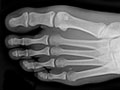

Una radiografía de las extremidades es una imagen de la mano, la muñeca, el brazo, el pie, el tobillo, la rodilla o la pierna. Se realiza para ver si se ha fracturado un hueso o si se ha dislocado una articulación. También se usa para ver si hay una lesión o un daño a causa de afecciones, como infección, artritis, crecimientos óseos (tumores) u otras enfermedades de los huesos como osteoporosis.

Una radiografía de las extremidades es una imagen de la mano, la muñeca, el brazo, el pie, el tobillo, la rodilla o la pierna. Se realiza para ver si se ha fracturado un hueso o si se ha dislocado una articulación. También se usa para ver si hay una lesión o un daño a causa de afecciones, como infección, artritis, crecimientos óseos (tumores) u otras enfermedades de los huesos como osteoporosis. En una emergencia, el médico puede observar los resultados iniciales de una radiografía de las extremidades en algunos minutos. En caso contrario, por lo general, un radiólogo tiene listo el informe oficial de la radiografía el día siguiente.

Los huesos o las articulaciones podrían mostrar señales de daño a causa de una enfermedad, como osteoporosis, artritis reumatoide, osteoartritis, gota o enfermedad de Paget. Vea imágenes de artritis reumatoide en los pies y artritis reumatoide en las manos.  |